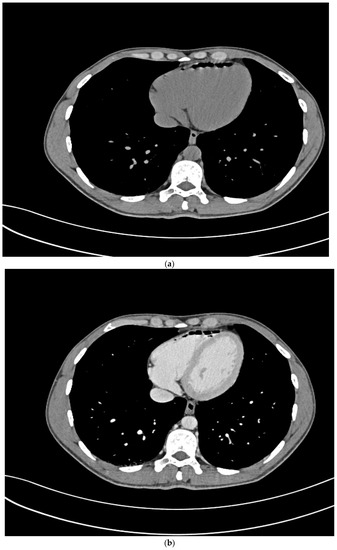

Due to a sudden worsening of the lesion to the lower limb, that was progressively involving the genital region, the patient also underwent a thigh and pelvis CT scan, which was negative for underlying infections, and a chest CT scan, resulting in a positive observation of an air bubble of a diameter of about 5 cm in the right ventricle (Figure 1a,b). For this reason, the patient was sent to our Hyperbaric Unit.

Figure 1.

(a) Pre-HBO: Chest CT scan w/o contrast medium and (b) with contrast medium.